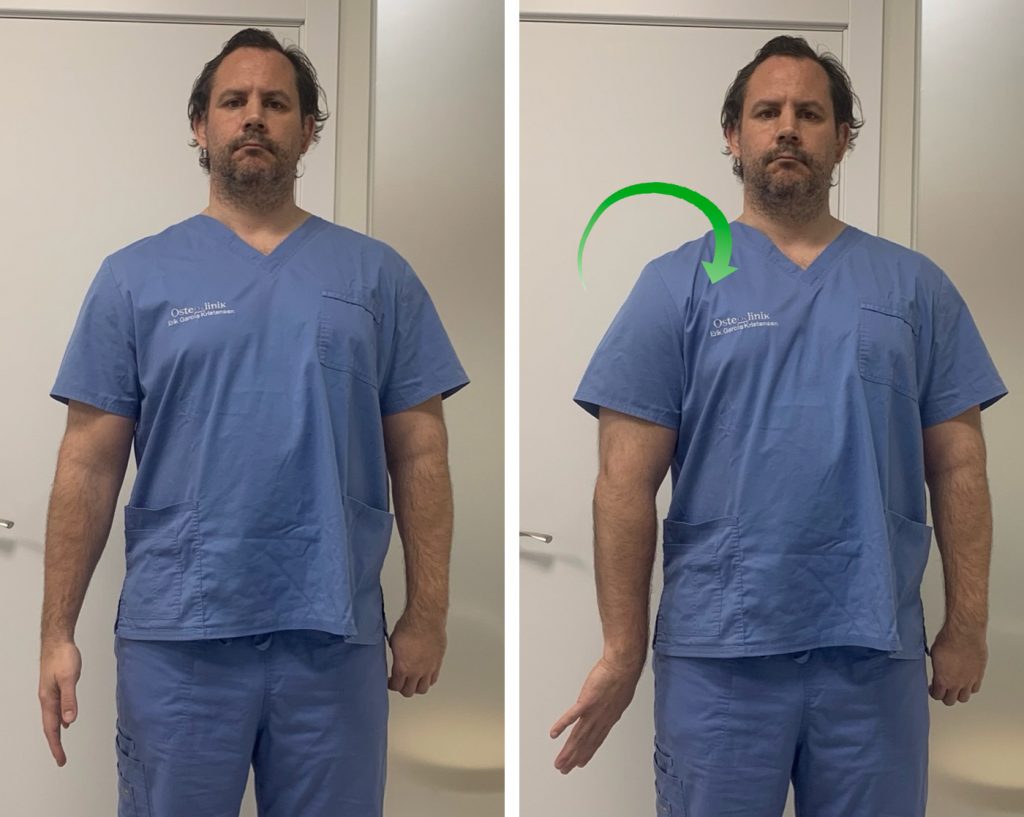

2. Nervio Radial

Vamos a realizar, primero, una puesta en tensión y estiramiento del nervio para después pasar a una movilización.

Partimos de una posición erguida de pie o sentado. Colocamos el brazo estirado y pegado a nuestro cuerpo. Seguidamente realizamos una rotación interna del hombro de forma que la palma de la mano quede mirando hacia lateral y el pulgar hacia atrás.

Nos aseguramos de descender el hombro para generar estiramiento entre las cervicales y el hombro.

Hacemos una flexión palmar de la muñeca e inclinamos lateralmente la cabeza hacia el lado contrario. De esta manera estamos poniendo en tensión el nervio mediano y podemos sentir la sensación de tensión y cierto hormigueo en el brazo y la mano.

Aguantamos unos segundos en esta posición y pasamos a trabajar el deslizamiento del nervio. Para ello, inclinamos la cabeza hacia el lado afecto (deberemos notar en este momento que desaparece la tensión y el hormigueo).

Y ahora volvemos a inclinar la cabeza hacia el lado contrario a la vez que hacemos una flexión dorsal de la muñeca. Cuando llegamos al límite de movimiento, inclinamos la cabeza de nuevo hacia el lado afecto y hacemos otra vez flexión palmar de la muñeca.

El ejercicio consiste en alternar inclinación contraria de la cabeza + flexión dorsal de la muñeca e inclinación hacia el lado de la lesión + flexión palmar.

Reposo

Estiramiento

Movilización- deslizamiento